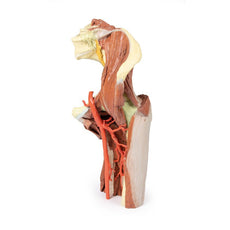

The sciatic nerve and great saphenous vein are also visible. The skin, superficial fascia, and deep fascia have been removed over the popliteal fossa to expose the contents of the space. The muscular borders of the space are intact except for a window cut into the semimembranosus muscle to allow a view of the popliteal artery and vein near the adductor magnus. On the medial aspect of the window the great saphenous vein descends on the surface of the sartorius muscle. Distally the sartorius is visible joining the semitendinosus and semimembranosus muscles to form the pes anserinus.

All major deep and superficial nerves and vessels of the space are visible, including the superior lateral genicular artery passing towards the anterior compartment of the thigh. Along the lateral margin the posterior aspect of iliotibial tract is visible descending to the lateral epicondyle of the tibia. The distal cross-section demonstrates the continuation of popliteal contents and branches. The great saphenous and small saphenous veins are visible within the superficial fascia, as are the medial and lateral sural cutaneous nerves.

Between the muscles of the posterior, lateral, and anterior compartments are the neurovascular bundles of the leg (posterior tibial artery, veins and tibial nerve; peroneal artery and veins; anterior tibial artery, veins and deep peroneal nerve; superficial peroneal nerve).

This 3D printed specimen preserves the distal thigh and proximal leg, dissected posteriorly to demonstrate the contents of the popliteal fossa and surrounding region. The proximal cross-section demonstrates the anterior, posterior and medial compartment muscles, with the femoral artery and vein visible within the adductor canal.The sciatic nerve and great saphenous vein are also visible. The skin, superficial fascia, and deep fascia have been removed over the popliteal fossa to expose the contents of the space. The muscular borders of the space are intact except for a window cut into the semimembranosus muscle to allow a view of the popliteal artery and vein near the adductor magnus. On the medial aspect of the window the great saphenous vein descends on the surface of the sartorius muscle. Distally the sartorius is visible joining the semitendinosus and semimembranosus muscles to form the pes anserinus.

All major deep and superficial nerves and vessels of the space are visible, including the superior lateral genicular artery passing towards the anterior compartment of the thigh. Along the lateral margin the posterior aspect of iliotibial tract is visible descending to the lateral epicondyle of the tibia. The distal cross-section demonstrates the continuation of popliteal contents and branches. The great saphenous and small saphenous veins are visible within the superficial fascia, as are the medial and lateral sural cutaneous nerves.

Between the muscles of the posterior, lateral, and anterior compartments are the neurovascular bundles of the leg (posterior tibial artery, veins and tibial nerve; peroneal artery and veins; anterior tibial artery, veins and deep peroneal nerve; superficial peroneal nerve).